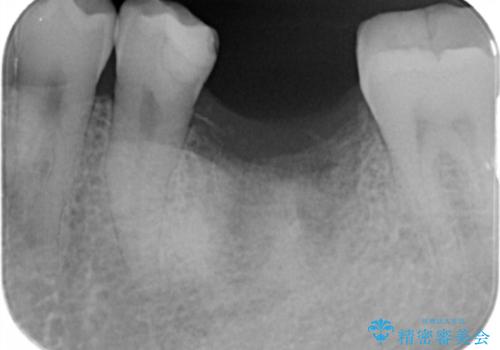

- 歯を破折により失い、インプラント治療を希望され来院されました。

インプラントを埋入し咬合機能を回復するとともに周囲の骨造成も同時に行っていきます。

インプラントを適切な位置に埋入することで、清掃性が高くしっかりと咬合力に耐えられるようなインプラント治療を行うことができます。